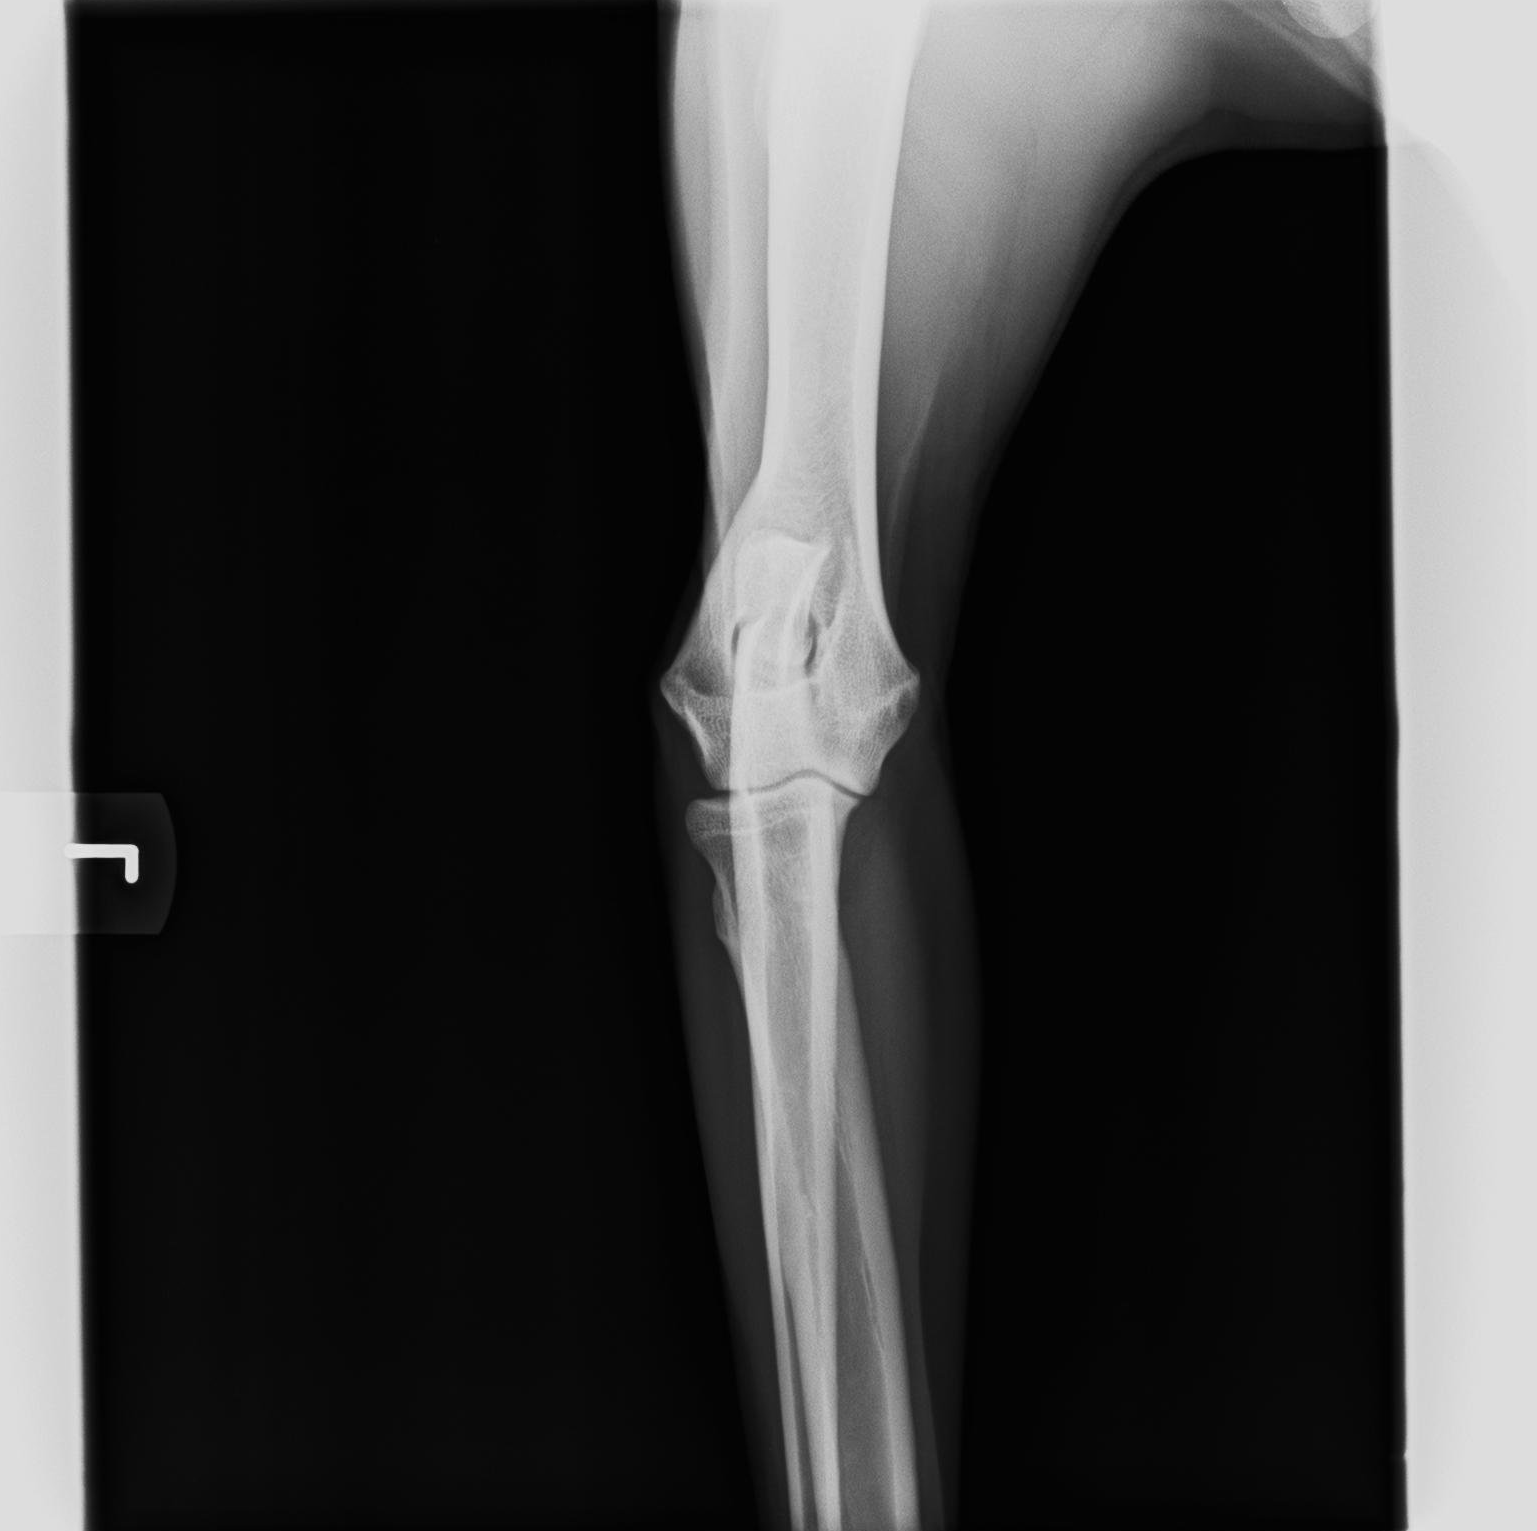

ED - Ellbogendysplasie

Die Ellenbogengelenksdysplasie (ED) ist ein chronisch verlaufender Krankheitskomplex des Ellenbogengelenks schnellwüchsiger Hunderassen. Die ED stellt eine vererbte Entwicklungsstörung des wachsenden Skeletts dar. Hohes Körpermassewachstum und Fütterungsfehler sind weitere begünstigende (prädisponierende) Faktoren. Die ED beginnt in der späten Wachstumsphase bei vier bis acht Monate alten Jungtieren mit einer schmerzhaften Veränderung des Gelenks und der gelenkbildenden Knochenteile (Osteoarthrose) mit Lahmheit. Der Bewegungsumfang des Ellenbogengelenks ist eingeschränkt. Frühzeichen sind Steifigkeit am Morgen oder nach Ruhepausen. Die Krankheit schreitet lebenslang fort und ist nicht heilbar, eine weitgehende Schmerzfreiheit kann aber in vielen Fällen erreicht werden.

Eine Ellbogendysplasie kann bei allen großwüchsigen Hunderassen auftreten. Die Häufigkeit des Auftretens beträgt bei einigen Rassen über 40 %.

Die ED wird polygenetisch (über mehrere Gene) vererbt. Der genaue Erbgang und die beteiligten Gene sind bislang nicht bekannt, so dass kein Gentest für die Erkrankung existiert. Der Nachweis kann daher bislang nur über die tierärztliche Beurteilung des Einzeltieres erfolgen, einige Hundezuchtverbände fordern eine Röntgenuntersuchung für Zuchttiere. Der Grad der Vererbbarkeit (Heritabilität) ist für Rüden größer als für Hündinnen und wird je nach Rasse und Population mit Werten zwischen 0,1 und 0,7 angegeben.

Die Röntgenbilder zeigen einen völlig gesunden Ellenbogen.